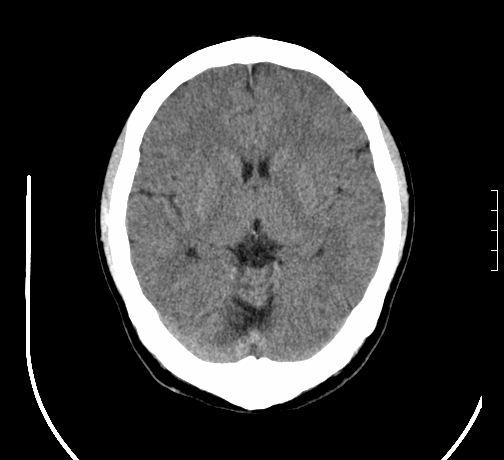

女,28岁,幼时有癫痫,常有发作,服药后可几月不发作,走路不稳3-4月,加重一月。

小脑发育畸形?

小脑萎缩。

考虑小脑发育不良,建议mri检查。

患者出现走路不稳是近几个月的事,而癫痫则有幼时就有,常发,则会常服药,癫痫药可引起小脑综合症,小脑萎缩,而小脑发育不良的主要症状不是癫痫

考虑癫痫,长期间断发服抗癫药,导致小脑综合症,小脑萎缩

考虑小脑发育不良伴小脑萎缩,建议mri检查。

小脑萎缩,原因待查,建议mri检查。